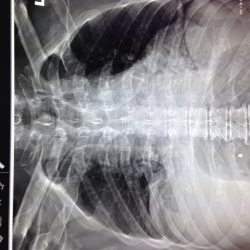

Заболел остро-одышка, боли за грудиной. Перенес год назад пневмонию в/доли пр.легкого-представляю R-контроль В настоящее время оп-ся R-признаки тотального просветления и дополнительная тень в 1...